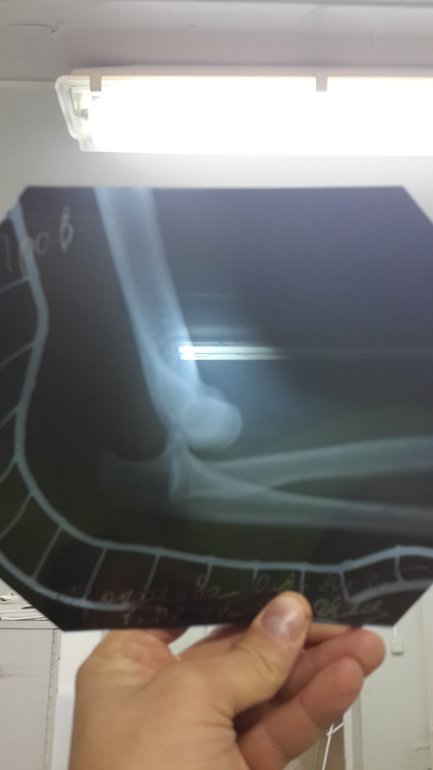

Так вот. Плохая "катучесть". Заход в поворот. Ошибка. Итог:

Между первым и вторым фото 3 часа где-то. Между ними - "бум", "АААА!", снегоход, шина, скорая, больница. И море, море слез, не зря же такой "мэйк-ап" у меня ))))

Не перелом, слава Богу, вывих. Но вправить на ледокаине не удалось, пришлось сделать что-то вроде спиналки на кесарево, только там ноги отключаются, а тут - рука. Уже после вправления доктор гипсует, рассказывает, что сустав нужно обездвижить, что снять гипс можно через три недели, что потом ЛФК и электрофорез и что-то там еще, и что этот сезон для меня закончен. Печалька, конечно. И тут я опомнилась! Аж подскочила. Доктор: "что такое!". Чтобы он не покрутил пальцем у виска на мое "и никакой вышивки месяц????!!!" промямлила, "эээ.... а как же душ?". Вот так вот. Хнык-хнык.